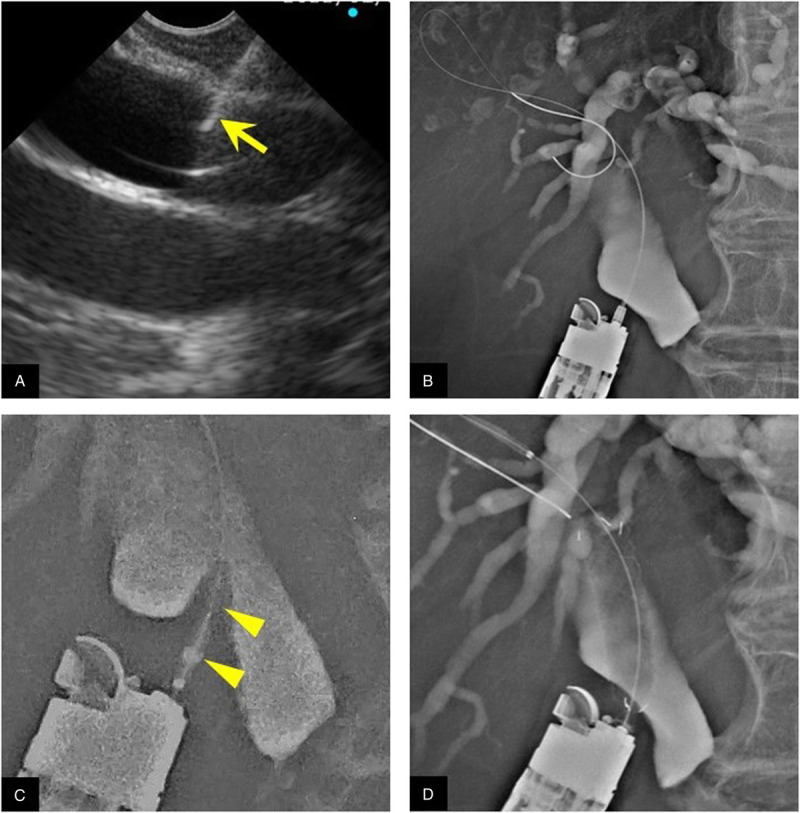

背景和目的:在eus引导下的胆总管十二指肠吻合术(EUS-CDS)中,置入支架前瘘口扩张与不良事件(ae)相关,如胆漏和腹膜炎。我们假设使用一种新型的自膨胀金属支架(SEMS)和薄输送系统无需瘘扩张的EUS-CDS可以克服这一问题,我们进行了这项研究来评估其可行性和安全性。方法:这是一项在单一机构进行的开放标签、单组、II期研究。我们计划使用全覆盖SEMS和5.9 fr输送系统进行EUS-CDS无瘘扩张治疗不可切除的恶性远端胆道梗阻。主要结果是总体技术上的成功。次要结果为技术成功,无瘘管扩张,手术时间,功能成功,复发胆道梗阻时间和ae。计划样本量为25例患者。结果:本研究共纳入24例患者。在21例患者中,EUS-CDS作为主要引流。总技术成功率为100%(24 / 24)。无瘘管扩张的技术成功率为96%(23 / 24)。手术时间中位数为16分钟(范围10-66分钟)。功能成功率为96%(23 / 24)。胆道梗阻复发的中位时间为148天(95%可信区间29-266天)。没有手术相关的不良反应。此外,手术后立即进行的计算机断层扫描显示,没有任何患者的造影剂渗漏到腹腔。结论:eus引导下全覆盖SEMS 5.9 fr输送系统无瘘扩张胆总管十二指肠吻合术是可行的,成功率高,可快速完成,有效预防胆漏和腹膜炎。

Background and objectives: During EUS-guided choledochoduodenostomy (EUS-CDS), fistula dilation before stent insertion is associated with adverse events (AEs), such as bile leakage and peritonitis. We hypothesized that EUS-CDS without fistula dilation using a novel self-expandable metal stent (SEMS) with a thin delivery system could overcome this problem, and we conducted this study to evaluate its feasibility and safety.

Methods: This was an open-label, single-arm, phase II study at a single institution. We planned EUS-CDS without fistula dilation using a fully covered SEMS with a 5.9-Fr delivery system for unresectable malignant distal biliary obstruction. The primary outcome was overall technical success. Secondary outcomes were technical success without fistula dilation, procedure time, functional success, time to recurrent biliary obstruction, and AEs. The planned sample size was 25 patients.

Results: In total, 24 patients were included in this study. In 21 patients, EUS-CDS was performed as primary drainage. The overall technical success rate was 100% (24 of 24 patients). The technical success rate without fistula dilation was 96% (23 of 24). The median procedure time was 16 min (range, 10-66 min). The functional success rate was 96% (23 of 24). The median time to recurrent biliary obstruction was 148 days (95% confidence interval, 29-266 days). There were no procedure-related AEs. Furthermore, computed tomography immediately after the procedure showed no leakage of contrast medium into the abdominal cavity in any patient.

Conclusions: EUS-guided choledochoduodenostomy without fistula dilation using a fully covered SEMS with a 5.9-Fr delivery system is feasible with a high probability and can be achieved quickly while effectively preventing bile leakage and peritonitis.